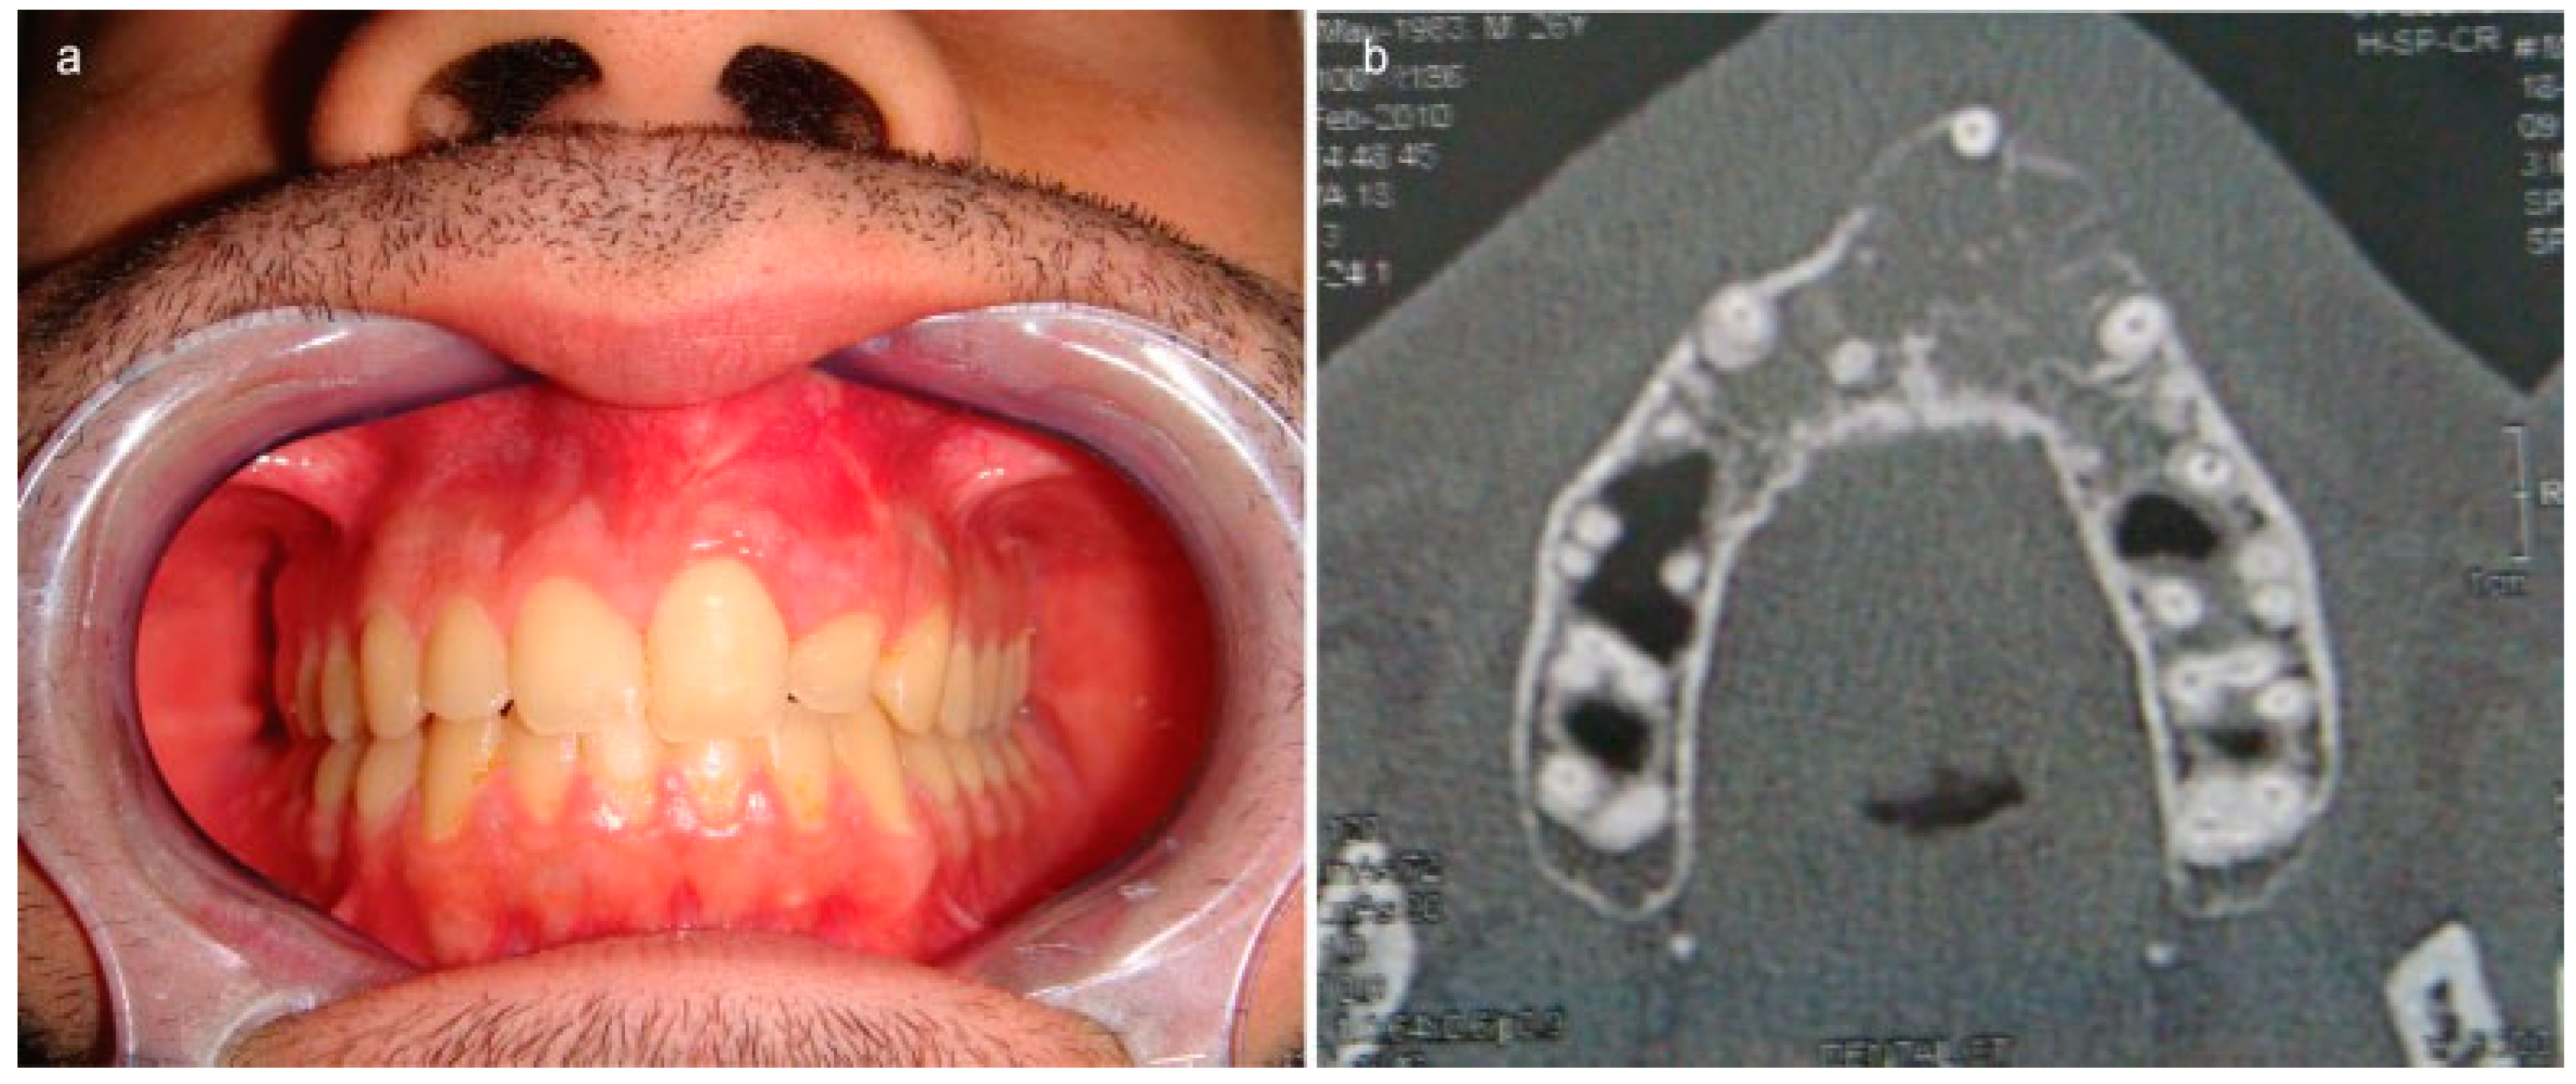

A 26-year-old male patient with a large bone tumor of the anterior maxilla extending between the right canine and left first premolar was treated (Figure 2a).

Clinical presentation was a painless swelling visible and palpable on the anterolateral upper sulcus detected during a routine consultation. CT scan (Figure 2b) revealed the bone expansive lesion with 2.7 cm diameter without involving soft tissues and the biopsy confirmed the diagnosis of odontogenic myxoma. Clinical and routine preoperative evaluations did not reveal any other pathology.

Figure 2. (a) Clinical presentation of a painless mass of left maxillary alveolar ridge. (b) Radiological presentation of an expansive disruptive bone lesion of anterior maxilla.